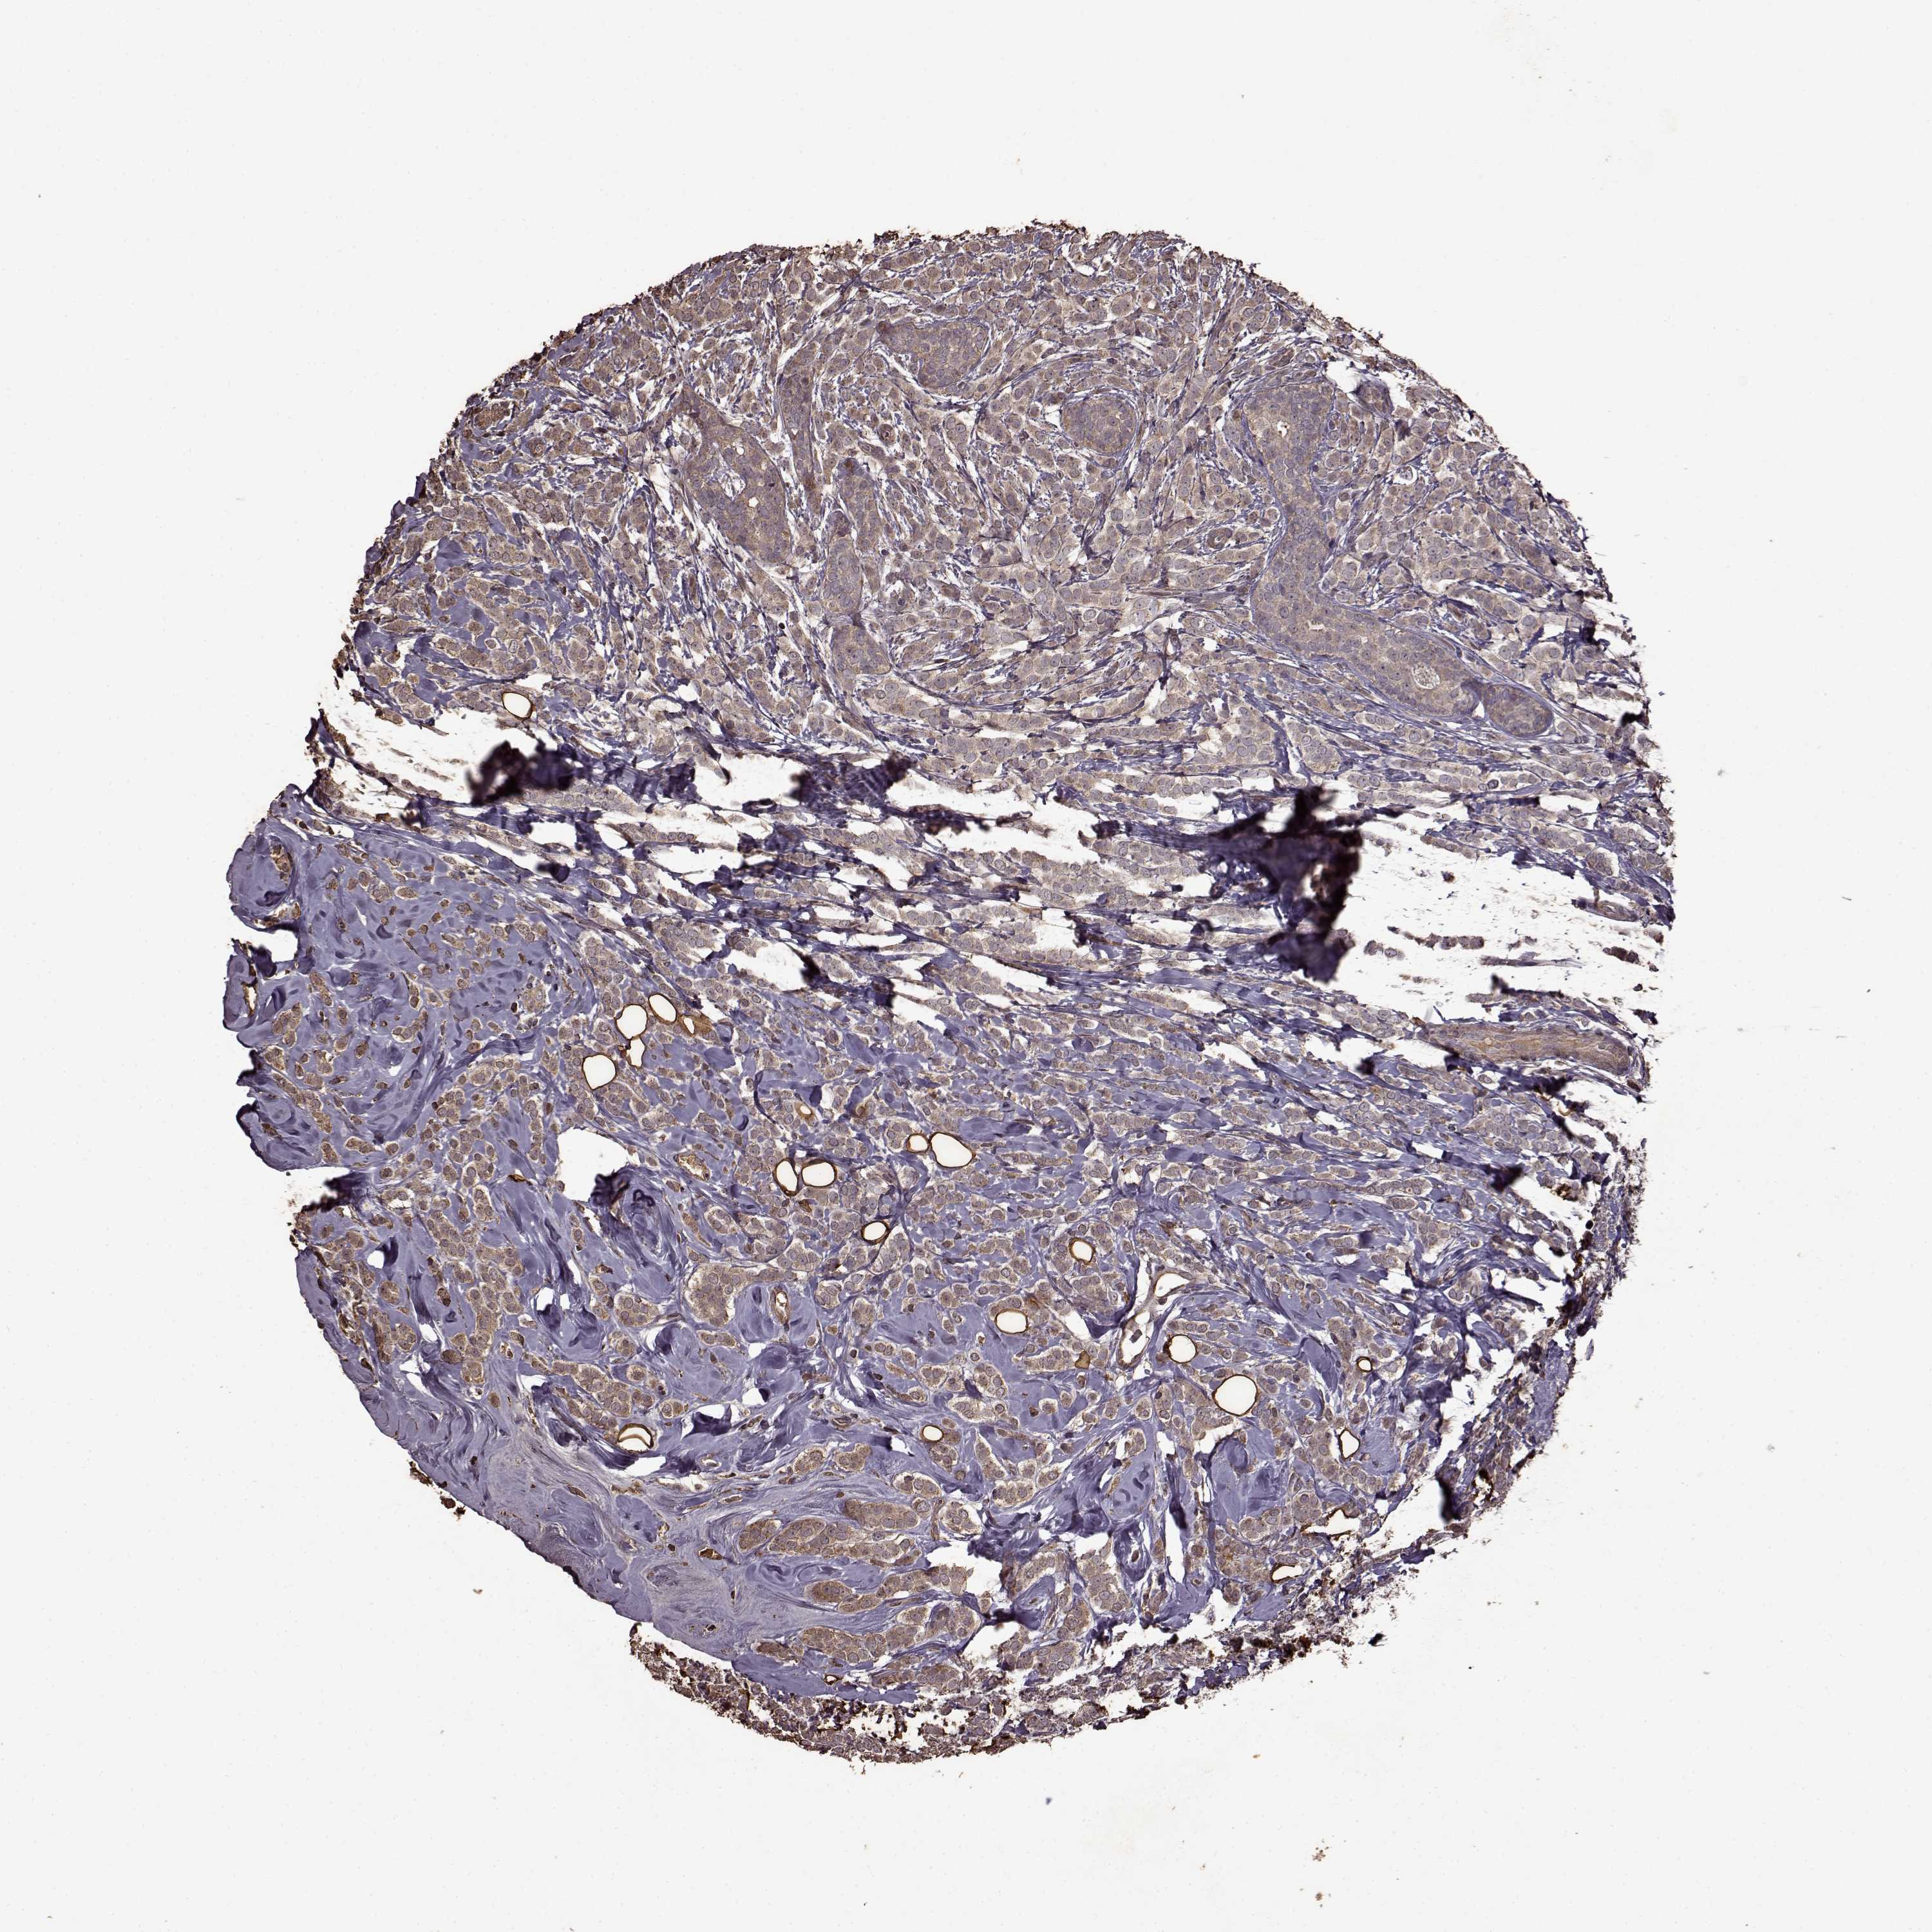

CANCER BREAST CANCER Show tissue menu

BRCA TCGA BRCA VALIDATION PROTEIN EXPRESSION